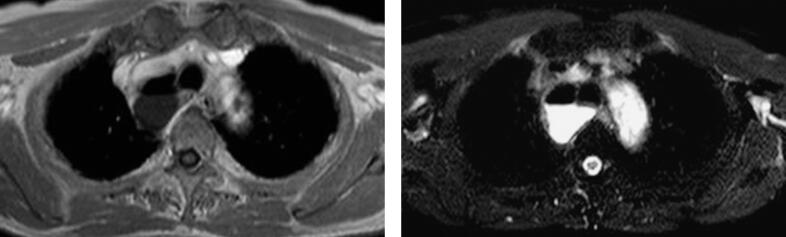

图1 右肺尖支气管囊肿

在磁共振图像上支气管囊肿表现为边缘清晰的薄壁囊腔,囊内气液含量差异带来影像表现不同,液体成分表现为典型的T1WI均匀低信号,T2WI均匀高信号,增强扫描不强化,囊壁不强化。